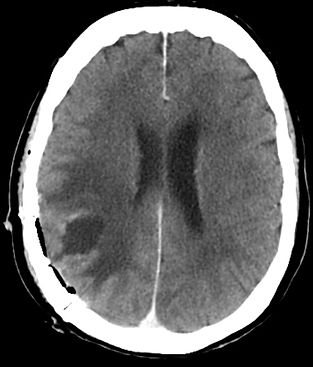

Spotāns intracerebrāls saasiņojums (hematoma)

Redzams saasiņojums smadzeņu vielā pirms operācijas

Pēcoperācijas attēls - saasiņojums no smadzenēm evakuēts